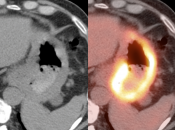

The difficulty with PET/CT imaging and gastric cancer is that it is both easy to overlook and easy to over-call.

Normal FDG uptake involving the stomach can be extremely variable. It is not uncommon to see diffuse intense uptake throughout the entire stomach or intense uptake limited to only a segment of the stomach (fundus, body or antrum).

In general, we raise a suspicion of gastric malignancy if:

• Focal or regional hypermetabolic activity is accompanied by at least the suggestion of associated wall thickening (often difficult to assess if the patient’s stomach is suboptimally distended with water or oral contrast);

• Uptake is extremely focal (more likely to represent malignancy or ulcer);

• Focal/segmental uptake is extremely intense.

• Obviously, signs of associated metastatic disease on the scan give the radiologist much greater confidence in reporting a suspected primary gastric lesion.